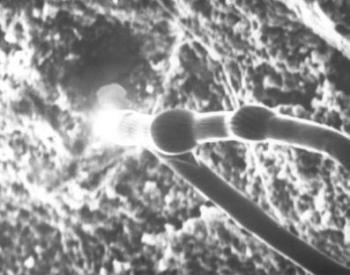

87. ábra. Basidiospórás gombatestek 19. századi fogkőben SEM 4900× nagyítás

A fogkövek vizsgálatát ritkán végzik, mindössze néhány tudósítás olvasható, noha a szájüreg flórájára, a táplálék minőségére, olykor a konyhatechnikára is felvilágosítást szolgáltathat. Dr. Török Katalin fogorvossal közösen végeztük el 20 váci múmia (30-68 év közöttiek) fogköveinek mikroszkópos elemzését. Valamennyiben kimutathatók Gram pozitív és negatív pálcák, Gram pozitív coccusok, de sohasem találtunk Gram negatív coccust. Három alkalommal gombatelepek illetve gombaspórák látszottak (85. ábra, 86. ábra, 87. ábra). Ez arra utal, hogy az idők folyamán jelentősen megváltozott az emberi szájflóra, ugyanis a neandervölgyi ember fogkövében csak pálca alakú baktériumokat (Pap és mtsai 1995 és 1996), egy ősindián temető anyagában viszont kizárólag coccusokat találtak (Magennis és Cummings 1996), a recens fogkövek mikroba összetétele fajgazdagabb (Silvestrini és mtsai 1992). A 18–19. században jelenhettek meg a gombák a szájüregben (10. táblázat). Roberts és Woodward (1996) két angliai temető leletein a fogkövek ételmaradványait tanulmányozva azt állítják, hogy nem lehetett lényeges különbség a lepratelep lakóinak és a telepen kívül élőknek a táplálkozása között. Magennis és mtsa (1996) mexikói ősindián populáció fogköveiben kukorica-keményítő szemcséket, perjefű-félék maradványait, fitolithokat azonosítottak. Valamennyi esetünkben növényi rostok, kristályok és fitolithok (90. ábra), kétharmadukban búza-, kukorica-, burgonyakeményítő szemcsék (89. ábra) fordultak elő, de rizskeményítővel sohasem találkoztunk. A 18–19. században mind a kukorica, mind a burgonya fontos néptáplálék lehetett. A fogkőbe zárt kollagénrostrészletek hőkárosodást mutattak, jelezvén, hogy nem nyers (kolbász, füstölt sonka, szalonna), hanem hőkezelt (sütött, vagy főzött) ételből származnak. Izomrostokat két alkalommal találtunk, számos képletet nem tudtunk azonosítani (85. ábra, 86. ábra, 87. ábra, 88. ábra, 89. ábra, 90. ábra).